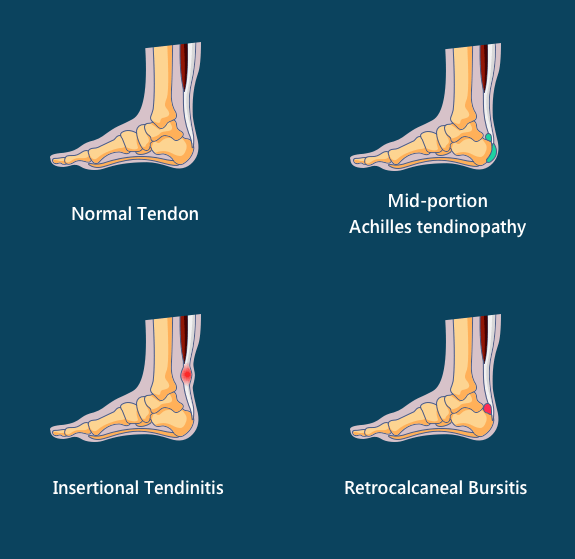

ACHILLES TENDINOPATHY – Step Relief Podiatry

What is Achilles Tendinopathy? – Insoles and Orthotics – Healthy Step

Achilles Tendinopathy (Tendinitis and Tendinosis) – Complete Feet …

Achilles Tendinopathy | Mr Daniel Goldbloom | Melbourne

Retrocalcaneal Bursitis: Causes, Symptoms & Treatment

Insertional Tendinitis Massage Treatment in the Achilles Tendon